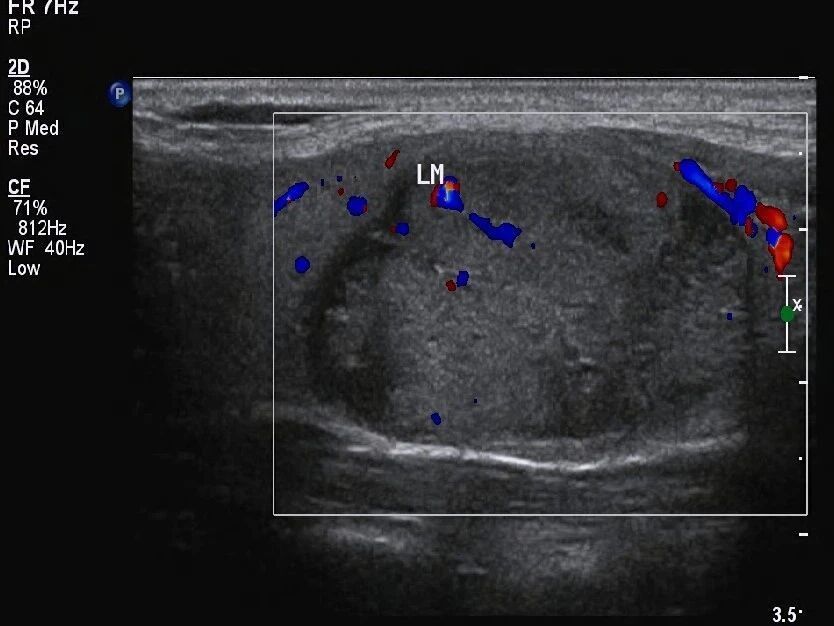

囊实性结节,存在包含液态的囊性部分,还存有含有固态的实性部分,这种具备混合结构的状况,给诊断带来特殊挑战,要留意的关键在于,其与由大量微小囊腔构成、基本没有实性成分的海绵状结节有着本质差别 。

在考量恶性风险时,结节全然呈现囊性状态,结节全然呈现海绵状模样,一般而言这种结节偏向良性,作为实性的结节,其风险相对较高,然而囊实性结节所具备的风险,处于这两者的范围区间之内,临床所获取的数据表明,囊实性结节致使恶变的概率,显著比完全呈现为实性样子的结节来得低。

结节在不同部位,那里出现了然点状强回声,而其临床意义有着截然不同的情况, 在位于囊性部分的体现为短线状强回声,尤其是伴有典型彗尾征的那种,大多是由浓缩胶质形成的,这属于良性表现,这些胶质实际上是甲状腺滤泡内浓缩的胶状性质物 。

点状强回声出现在实性部分时,此显示情况下其后方没有清楚明显的彗尾征,这时需十分密切高度警惕微钙化存在的可能性,在这样的状况下,即便结节其他特征表现展示良好,也应按可疑特征样式处理应对,还建议更进一步深入检查明确定性质,。